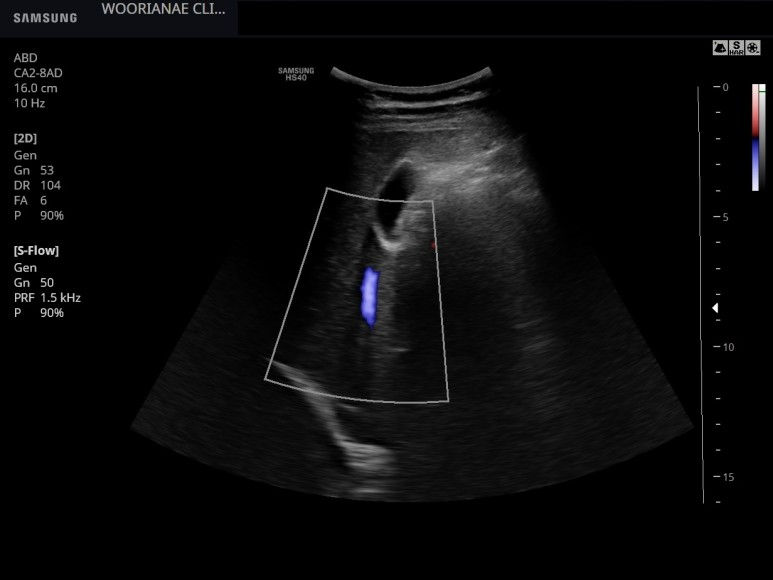

2월 내원시 추적 모습

공복이 아니기 때문에 담낭은 충분히 담즙으로 차 있지 않으며 벽이 두꺼워 보인다.

view가 좋지 않아 이전에 용종은 관찰되지 않으며 담석의 증거는 없다.